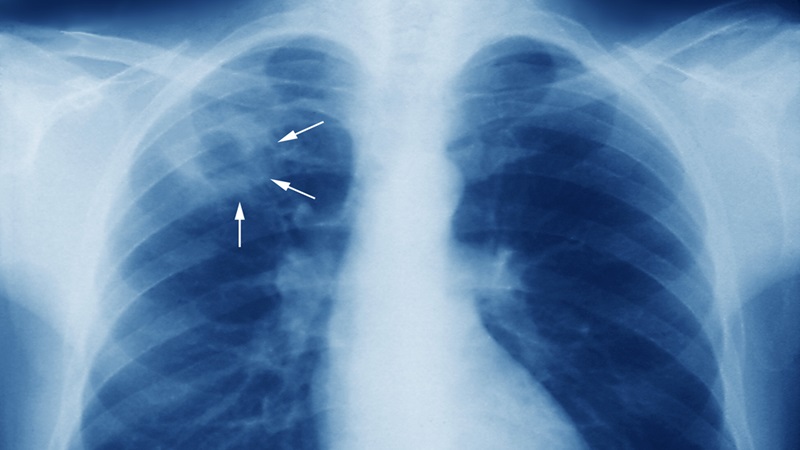

Thông qua hình ảnh X-quang của lao phổi, bác sĩ có thể phân biệt bệnh lý này với nhiều vấn đề sức khỏe khác và đánh giá chính xác tình trạng bệnh người được thăm khám.

Những người có nghi ngờ mắc lao phổi thường được bác sĩ chỉ định chụp X-quang để chẩn đoán và xác định chính xác giai đoạn bệnh. Vậy hình ảnh X-quang của lao phổi có điểm gì đặc biệt? Bài viết dưới đây của Nhà thuốc Long Châu sẽ làm rõ nghi vấn này.

Đối với những trường hợp nghi ngờ mắc lao phổi, chụp X-quang ngực được xem là kỹ thuật xét nghiệm hình ảnh bắt buộc.

Phương pháp này có độ nhạy cao, dễ áp dụng rộng rãi trong sàng lọc lao phổi. Hình ảnh tổn thương do lao phổi thể hiện rất rõ nét trên phim X-quang. Vậy nên bác sĩ có thể dựa vào xét nghiệm này để có thêm căn cứ khi chẩn đoán.

Tuy vậy, phim chụp X-quang có độ đặc hiệu không quá cao. Vậy nên để gia tăng độ tin cậy của kết quả chẩn đoán, các chuyên gia y tế thường kết hợp kỹ thuật xét nghiệm này với nhiều phương pháp khác như nhuộm soi tiêu bản đờm, chụp Xpert MTB, nuôi khuẩn lao, thử phản ứng Tuberculin.

Hình ảnh X-quang của lao phổi không giống nhau hoàn toàn ở các ca bệnh mà chỉ có 60 - 80% điểm tương đồng. Đặc biệt, các loại lao phổi khác nhau sẽ cho hình ảnh X-quang khác nhau.